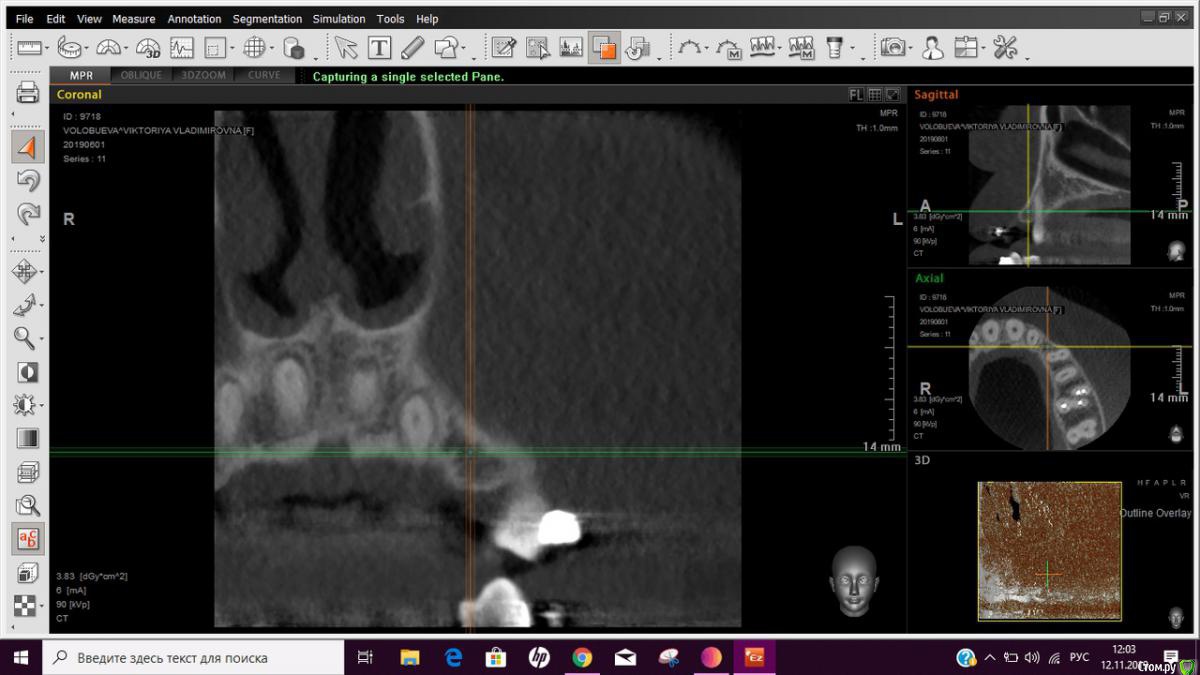

Виктория В. Опубликовано 1 декабря, 2019 Автор Поделиться Опубликовано 1 декабря, 2019 (изменено) Десна подтянулась и стало ощущаться. Так было всегда ,просто не замечали Это нормально. Такая анатомия. Тонкий биотип. Вероятно с правой стороны аналогично и в целом от 15 до 25 могут прощупываться. без объективных данных ответить не получитсяЗдравствуйте доктора, сегодня сделала наконец-то КТ, потому что чувствую, что зуб (4) начал выпирать вперед еще больше, на неделе пойду к хирургу, вариант нормы и так было - точно нет, на снимке видно, что имплант все таки задел корень, как я и говорила по своим ощущениям, + корень реально выходит вперед, в отличает от основного ряда. Вопрос: что делать? Каких действий мне нужно ожидать от лечащего врача, чтобы это было корректно, чтобы не сказали, что все круто, ничего менять не нужно, а потом у меня выпадет здоровый зуб (начиталась веток на форуме). Допустимо ли такое расположение? Дальнейшие действия подскажите, пожалуйста, требуется переимплантация или что? Заранее всем большое спасибо! Изменено 1 декабря, 2019 пользователем Виктория В. Ссылка на комментарий

Виктория В. Опубликовано 1 декабря, 2019 Автор Поделиться Опубликовано 1 декабря, 2019 Вот еще снимок, где видно, как корень сильно выпирает Ссылка на комментарий

Irouil Опубликовано 1 декабря, 2019 Поделиться Опубликовано 1 декабря, 2019 Если Вы ожидаете, что лечащий врач может Вам "навешать лапшы", то стоит менять врача, независимо от результатов его работы. Найдите такого специалиста, которому сможете довериться. На представленных срезах имплантат находится близко к корню соседнего зуба, но не повреждает его. Перемещения зуба скорее могут быть связаны с ортодонтическим лечением, которое Вы проходите, имплантация тут, на мой взгляд, вообще не при чем 1 Ссылка на комментарий

Виктория В. Опубликовано 1 декабря, 2019 Автор Поделиться Опубликовано 1 декабря, 2019 Приложу еще срезы КТ, мне кажется имплант не просто рядом, а он задел корень, и в этом месте видно, как выталкивает его. Я права, или мне кажется? Какие дальнейшие действия тут могут быть Ссылка на комментарий

Irouil Опубликовано 1 декабря, 2019 Поделиться Опубликовано 1 декабря, 2019 Возможно - задел, но это не должно приводить к смещению зуба. Наоборот - имплантат абсолютно неподвижен в тканях, в отличии от зубов. С ортодонтом говорили по этому поводу? Ссылка на комментарий